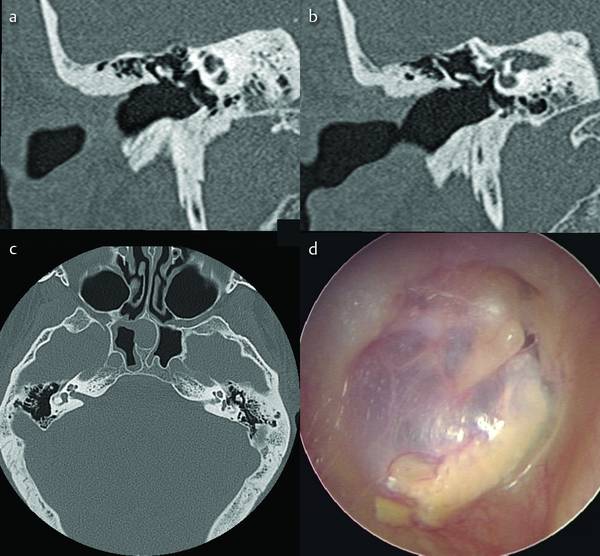

Рис. Рентгенограмма пирамиды левой височной кости больного холестеатомой уха (в проекции по Майеру): стрелкой указан овальной формы дефект в области надбарабанного углубления со склеротическими изменениями по периферии, обусловленный холестеатомой.Важное диагностическое значение в сочетании с клин, данными имеет рентгенологическое исследование. Рентгенографию височной кости производят в специальных проекциях (см. Среднее ухо). Ценные дополнительные сведения могут быть получены при томографии височных костей в прямой и боковой проекциях (см. Краниография). Рентгенологическая картина зависит от размеров и локализации холестеатомы уха, которая распознается по вторичным признакам — изменениям в прилежащих костных структурах. Небольшие холестеатомы могут не давать рентгенологической симптоматики. Крупная холестеатома приводит к увеличению размеров сосцевидной пещеры и надбарабанного углубления, истончению и разрушению наружной стенки последнего и входа в сосцевидную пещеру. Контуры дефекта кости, образованного неосложненной холестеатомой, четкие, дефект имеет округлую или полигональную форму с небольшой склеротической полоской по периферии (рис.). Отсутствие четкой и плотной капсулы холестеатомы является рентгенологическим признаком обострения процесса.

- Компьютерная томография височной кости — можно увидеть костную эрозию височной кости, сопровождающей мягкие ткани среднего уха. КТ — наиболее специфический тест, но он требует значительного облучения. Когда диагноз холестеатомы уже установлен (возможно, требуется рецидив), лучше выбрать DWI MRI.

Вышеупомянутая корональная компьютерная томография была сделана пациенту после мастоидэктомии (стенка канала опущена) и показывает рецидив холестеатомы.